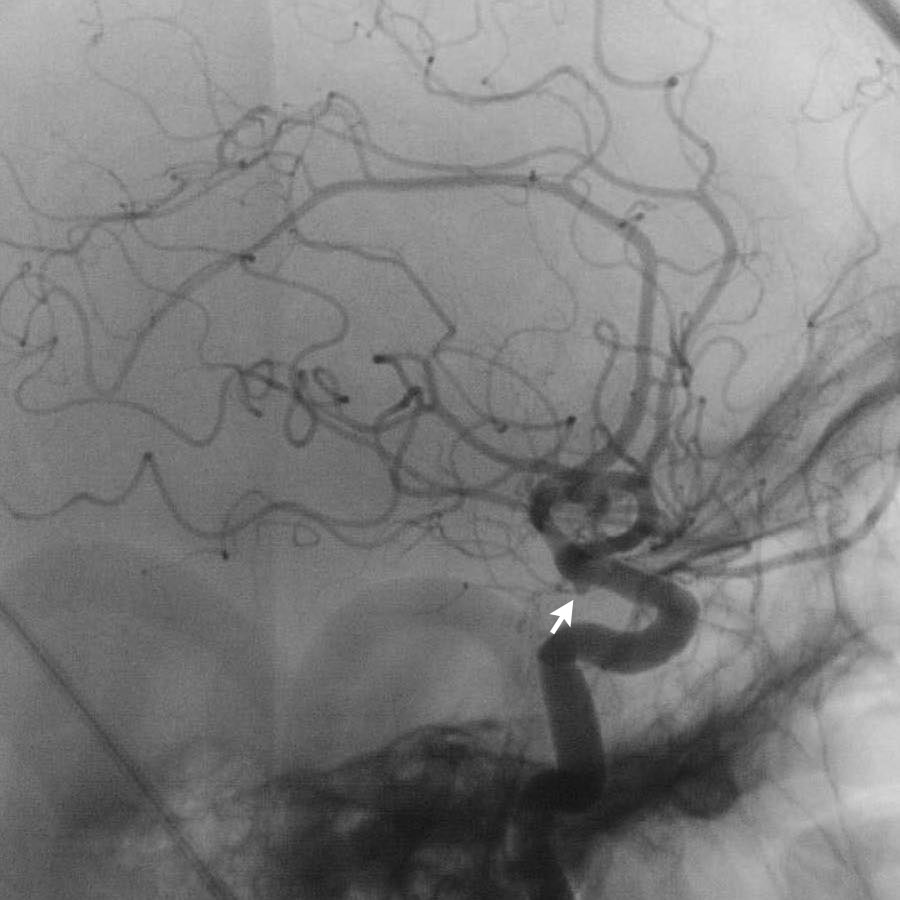

Các hình ảnh cho thấy DSA trước và sau khi đặt coil túi phình.

PICA, nidus và các tĩnh mạch dẫn lưu bất thường (cùng tạo thành AVM) vẫn còn ngấm thuốc tương phản.

Quyết định không điều trị trực tiếp AVM mà lựa chọn theo dõi và có thể can thiệp phẫu thuật trong tương lai.

Hình bên trái: DSA túi phình trước điều trị.

Hình bên phải: DSA sau điều trị bằng đặt coil riêng biệt cho túi phình chính và túi phình con (mũi tên vàng).

Quyết định điều trị túi phình trước và phẫu thuật cắt bỏ AVM trong giai đoạn bán cấp khi bệnh nhân đã hồi phục sau xuất huyết dưới nhện.